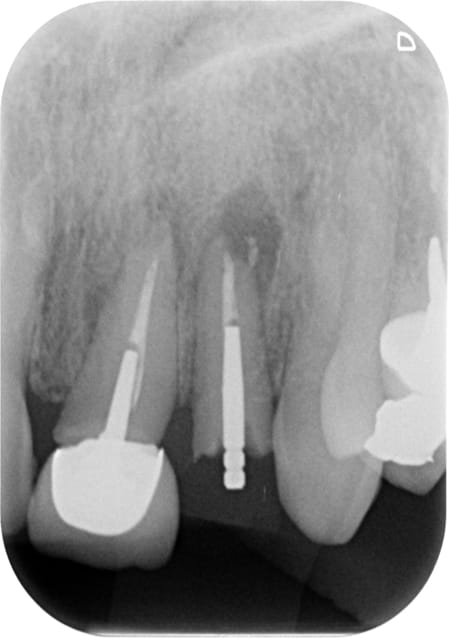

J'ai pas encore le scan

La corticale vestibulaire est présente sauf en regard de la lésion

L'occlusion est en classe I

Est ce que c'est raisonnable de faire une implantaion immédiate le jour de l'extraction avec un bon curetage de la lésion ?

T'as beaucoup de hauteur d'os au dessus de ta lesion, alors...pourquoi pas si t'es bon en largeur, et que tu garde des tissus mous en bon etats.

Tu peux envisager l'extraction implantation en curetant bien mais fais bien attention tu as apparamment aussi une lésion sur la dent adjacente.

Tu pourrais avoir un échec à cause de cette lésion que tu n'aura pas traitée et non pas à cause de ton extraction implantation.

endo avant implantation et pourquoi pas endo extract puis à distance (6 sem.) tu implante (assez long car tu as de l'os

Perso je déposerai la couronne et tenterai un retraitement,

si c'est ok j'attendrai 5/6 semaines puis extraction implantation,

ou alors endo puis dans la même séance extraction et implant 6 semaines plus tard.

si endo pas ok, je déciderai d'extraire les 2 dents;

En fait si le retraitement se passe bien, bonne perméabilité canalaire et obturation étanche, tu peux extraire la dent non conservable dans la même séance.

Et implanter 6 semaines plus tard.

Si le retraitement ne se passe pas bien, envisager l'extraction et l'implantation des 2 dents en même temps dans une séance ultérieure.

Concernant la remarque de Béotien, pas d'extraction implantation après le traitement canalaire car la lésion n'est pas guérie, il faut attendre min 6 semaines avant d'implanter pour éviter de perdre l'implant.